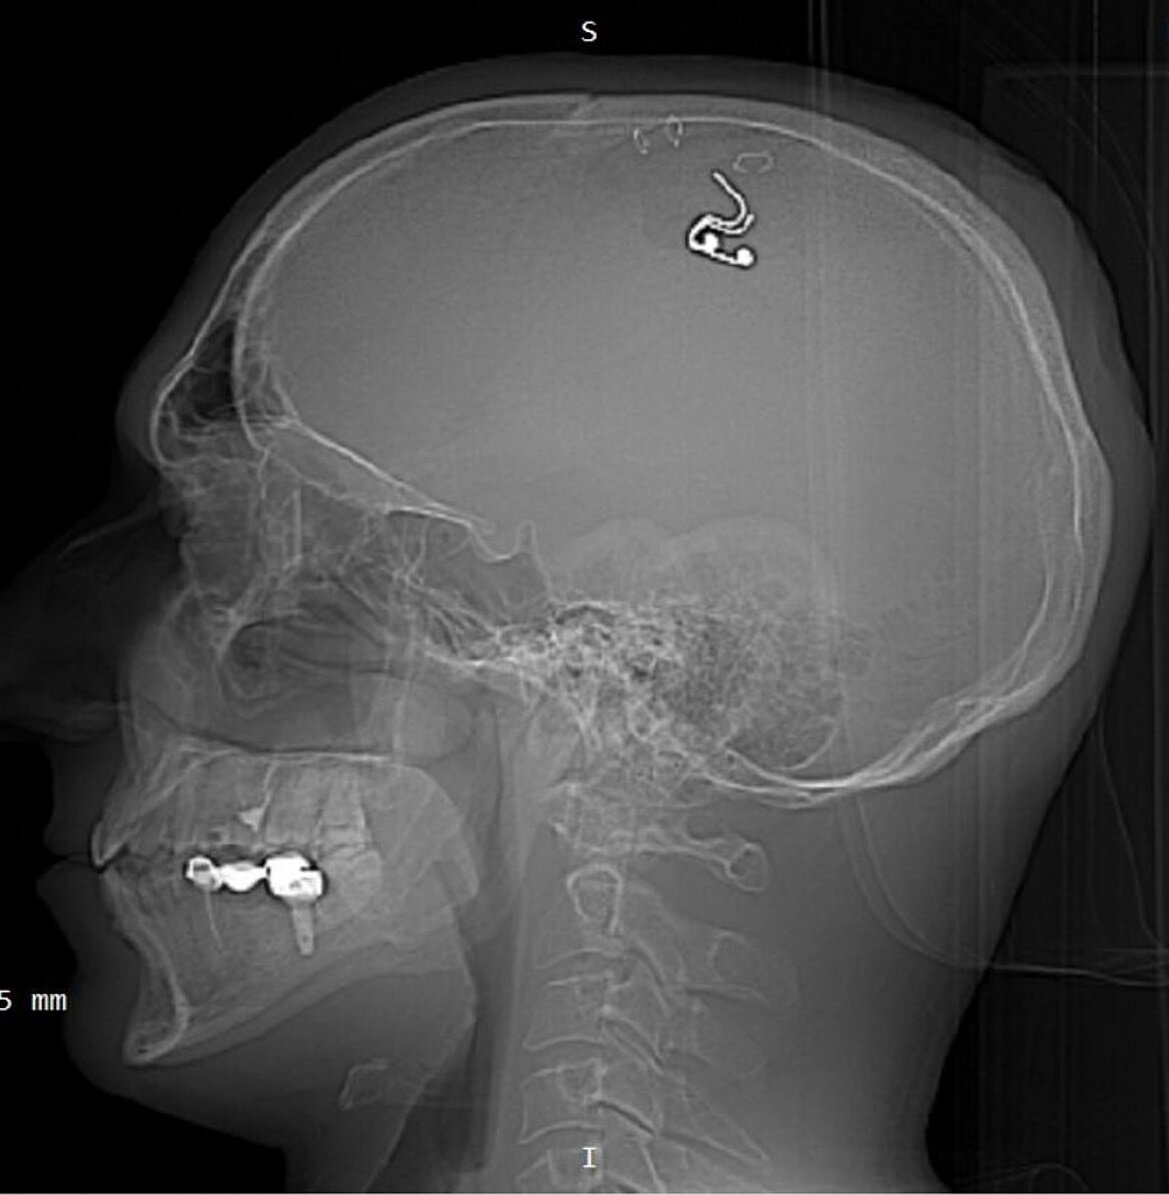

Такой снимок выложил в сеть Михаил. Фото: t.me/misha_raduga

- В первые полчаса я готов был сдаться в любую минуту. Потерял много крови, боялся, что потеряю сознание. Но всё-таки я пересилил себя, не сдался и продолжил. Сделал трепанацию и на проекцию моторной части коры мозга положил электроды. Провёл ток туда и зашил всё это.